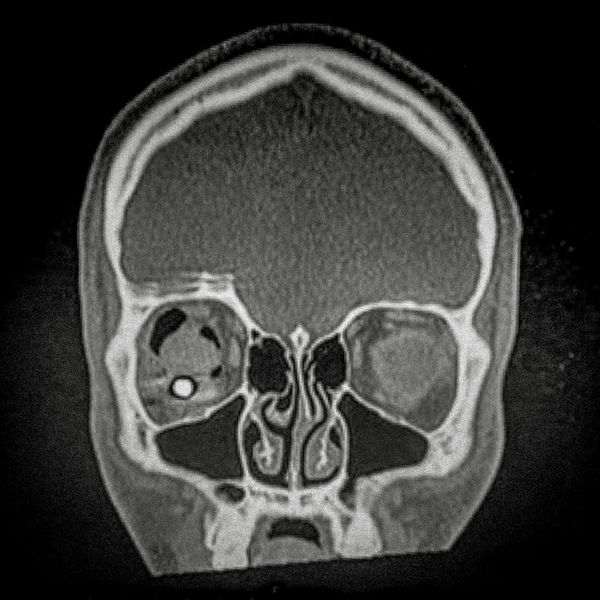

460 people have been seriously injured in their eyes, 34 of whom suffered total loss due to the indiscriminate use of pellets and tear gas bombs by the Carabineros de Chile special forces. The Carabineros fired their rubber bullets and tear gas guns directly into the faces of the protesters during the Chilean social outbreak between late 2019 and early 2020. This figure has made Chile the country with the world record for eye mutilation by state and security forces.

By early March 2020, around 3,838 people had been injured and according to the Chilean Society of Ophthalmologists and human rights organizations, 460 of them ended up with serious eye complications, loss of the eyeball, and also loss of sight. This figure has made Chile a world record for eye mutilation, due to the indiscriminate use of pellets and tear gas bombs by special forces of the Carabineros, who have shot their weapons directly into the faces of the protesters.